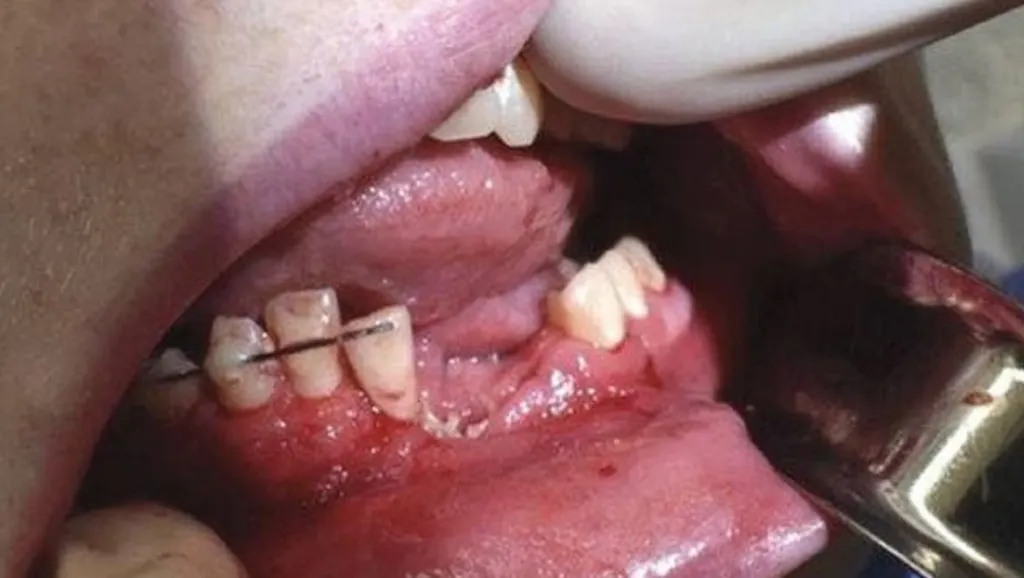

Так выглядел рот Остина Адамса после того, как взорвался вейп

Вейп марки VGOD подростку купила его мать – так женщина хотела помочь сыну бросить курить сигареты. При первом же использовании устройство взорвалось, повредив парню челюсть и выбив несколько зубов. Также на лице Остина остались ожоги.